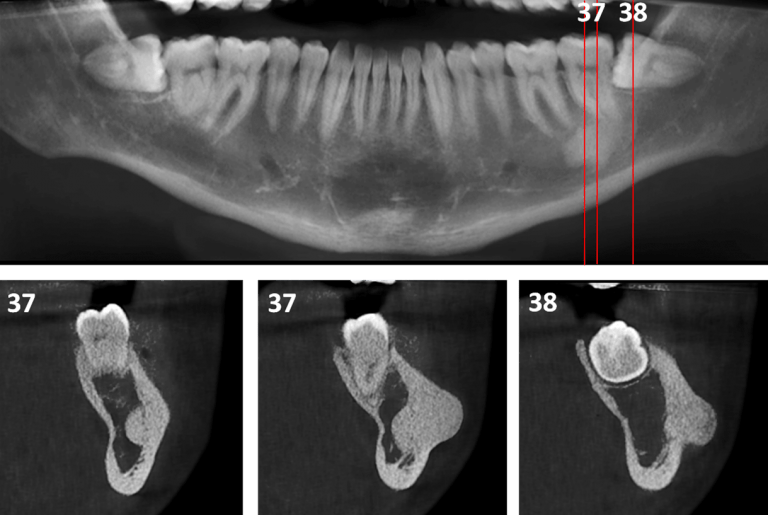

From www.jem-journal.com

Mandibular Osteoid Osteoma Journal of Emergency Medicine Osteoma Dental Treatment Osteoid osteoma is a benign tumor in your shin, thigh or other bones. In some cases, dental extractions may be necessary to address an osteoma and restore oral health. Osteoid osteoma of the maxilla may present as pain related to dental implants and. Treatments for osteoma include pain relief and monitoring, surgery, and radiofrequency. The recommended treatment for osteoblastoma and. Osteoma Dental Treatment.